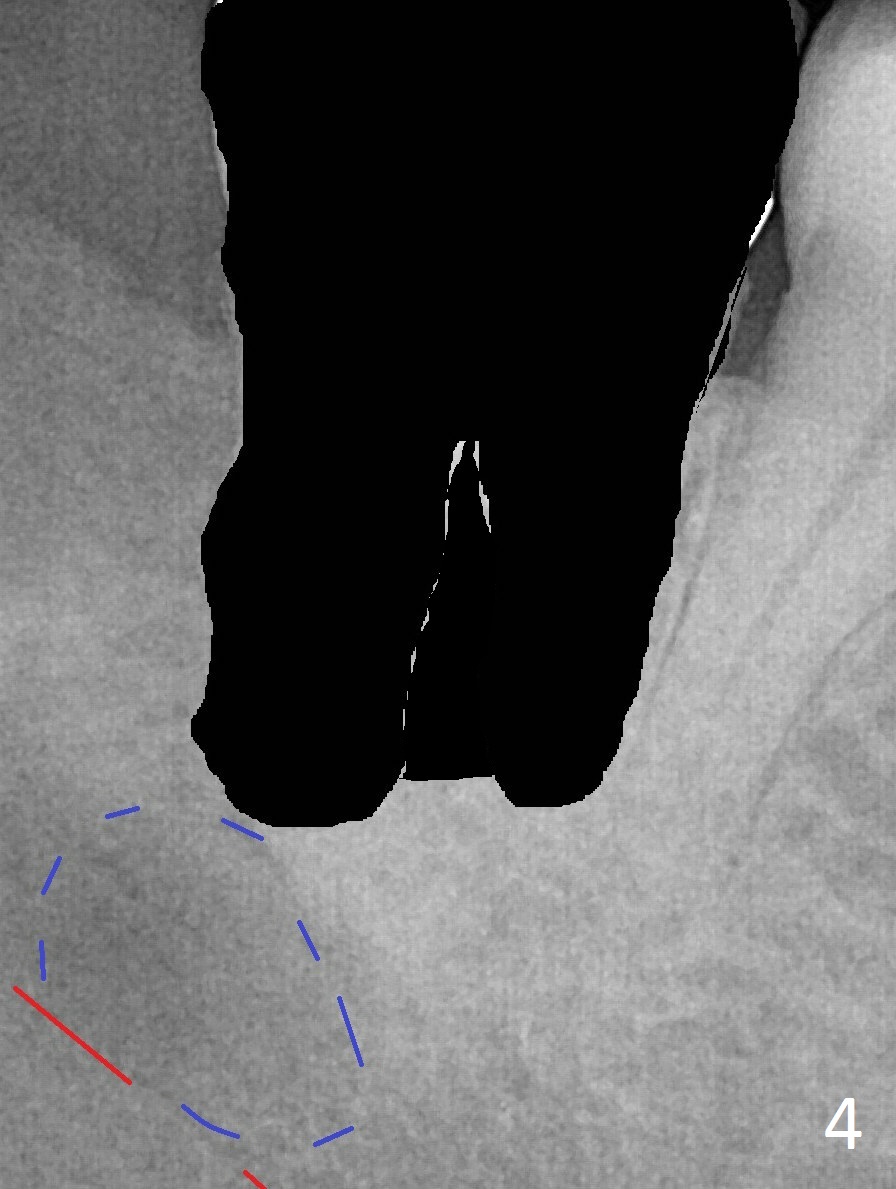

Abscess from #32 or 31?

A 45-year-old woman presents to clinic with swelling and pain from the lower right posterior region. The tooth #32 is fully bony impacted. The distolingual gingiva of #31 is erythematous with deep pocket. The tooth is sensitive to percussion. Preop panoramic X-ray shows a radiolucent lesion between #31 and #32 (Fig.1 blue dashed line). Initial impression is infection from #32. Extraction of the latter turns out to be difficult. Purulent discharge is coming from underneath the coronal portion of the tooth. Curettage of the radiolucent lesion leads to hemorrhage. The curettage is not aggressive because of the underlying Inferior Alveolar Canal (red dashed line). Following copious irrigation, a 10x20 mm Osteogen plug is inserted into the socket with incision closure. Postop PA reveals that the roots the teeth #31 and 30 approximate to each other (Fig.2 R). In case the tooth #31 needs to be removed (Fig.3 black area), osteotomy for immediate implant will be established in the middle of the septal stump (Fig.5 red arrow) after removal of the coronal septum (Fig.4). CBCT may be necessary for determination of the osteotomy depth.